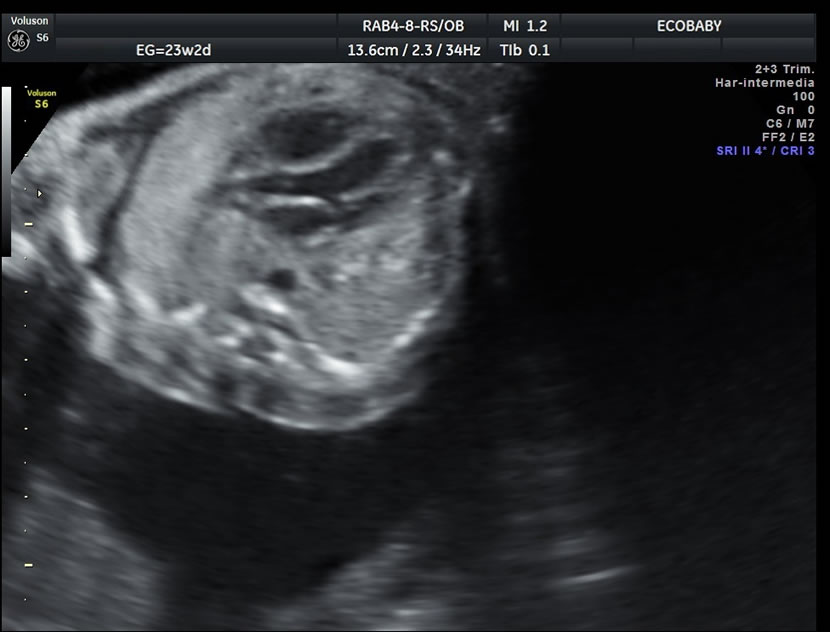

Se efectúa entre las semanas 20 y 24 aunque de ser necesario puede diferirse un poco. Más allá de las 30 semanas el tamaño del bebe y las sombras que ocasionan sus huesos impiden la visualización completa.

Cerebro, cuello, cara, tórax, corazón (diferentes cortes que muestran las cavidades y la correcta entrada y salida de arterias y venas), abdomen (normalidad de la pared, estómago, intestino, riñones, vejiga), miembros inferiores y superiores y columna vertebral.